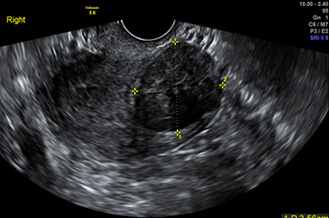

正常な子宮